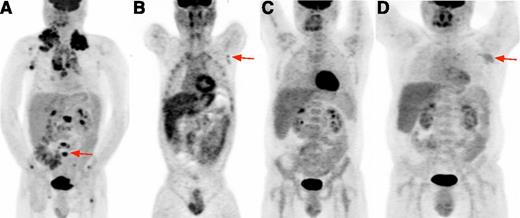

A 44-year-old man was referred with relapsed HIV-cHL. He initially presented 20 months prior with supraclavicular swelling, night sweats, and weight loss. Excisional lymph node biopsy demonstrated Epstein-Barr virus (EBV)-associated cHL, mixed cellularity (MC) subtype (Figure 1). HIV serology revealed the previously undiagnosed infection. CD4+ T-cell count (CD4+ count) was 140 cells per mm3. He commenced tenofovir, lamivudine, and ritonavir-boosted atazanavir for HIV, as well as trimethoprim/sulfamethoxazole for Pneumocystis pneumonia prophylaxis. He had no history of opportunistic infections (OIs). 18Fluorodeoxyglucose (18FDG) positron emission tomography (PET) revealed 18FDG uptake in lymph nodes and bones (Figure 2A). He had advanced-stage, unfavorable disease (stage IVB and International Prognosis Score of 4 based on gender, stage, hemoglobin level of 10 mg/dL, and albumin level of 2.0 mg/dL). He received doxorubicin, bleomycin, vinblastine, and dacarbazine (ABVD) with pegfilgrastim and continued cART. His first cycle was complicated by grade 4 neutropenic fever lasting 2 weeks. During subsequent cycles, vinblastine and dacarbazine were dose reduced by 50%. Additionally, there were dose delays during several cycles due to neutropenia, and the patient developed grade 2 neuropathy. 18FDG-PET after 2 cycles showed uptake in the left axilla. A biopsy sample taken in response to a solitary radiographic lymph node abnormality after 6 28-day cycles showed reactive changes. He completed 8 cycles and achieved a complete response (CR). After therapy, CD4+ count was 173 cells per mm3.

18FDG-PET in HIV-cHL. (A) Baseline 18FDG-PET. Volumetric image shows bulky intensely hypermetabolic cervical, mediastinal, and axillary lymph nodes and multiple focal bone lesions (representative vertebral lesion, red arrow). (B) Interim 18FDG-PET. At the end of cycle 2, coronal image focuses on a small suspicious lesion in left axilla (red arrow); diffuse bone uptake attributable to pegfilgrastim is also noted. After cycle 6, a biopsy sample of residual abnormalities in the left axilla showed reactive changes and no evidence of cHL. (C) End-of-therapy 18FDG-PET. Volumetric image shows resolution of 18FDG avid nodes. (D) Relapse 18FDG-PET. Volumetric image shows left axillary avid lymph node (red arrow) and other small nodes above the diaphragm.

Twelve months after completing chemotherapy, a new axillary lymph node was palpated. Computerized tomography (CT) revealed a 2.5-cm axillary lymph node and other new, smaller lymph nodes. Excisional biopsy revealed recurrent EBV-positive (EBV+) cHL lymphoma, MC subtype. CD4+ count was 145 cells per mm3 and HIV viral load remained undetectable. 18FDG-PET revealed no extranodal disease (Figure 2D). We reasoned that drug-drug interactions between HIV protease inhibitor (PI)-based therapy and vinblastine complicated his initial treatment, and that although he had recurrent disease at 12 months, it was likely chemosensitive owing to initial response despite prior dose reductions and cycle delays. Therefore, to reduce drug-drug interactions, we modified his cART, replacing ritonavir and atazanavir with efavirenz. Given his prior intolerance to therapy, we elected to employ dose-adjusted etoposide, doxorubicin, vincristine, cyclophosphamide, prednisone, and filgrastim rather than conventional cHL salvage. We anticipated that vincristine would be less affected by efavirenz than would be the case with vinblastine, and that dose intensity could be adjusted based on the prior cycle. Due to the low-dose prolonged infusions, we anticipated minimal cardiac toxicity from additional doxorubicin. After 2 cycles, CT showed no disease, and he proceeded to autologous stem cell transplant (auto-SCT) following carmustine, etoposide, cytarabine, and melphalan conditioning. CD4+ count 3 months posttransplant was 186 cells per mm3. The patient has been followed on cART for 7 years with no relapse, undetectable HIV with CD4+ count rising to >500 cells per mm3, and resolution of his neuropathy.